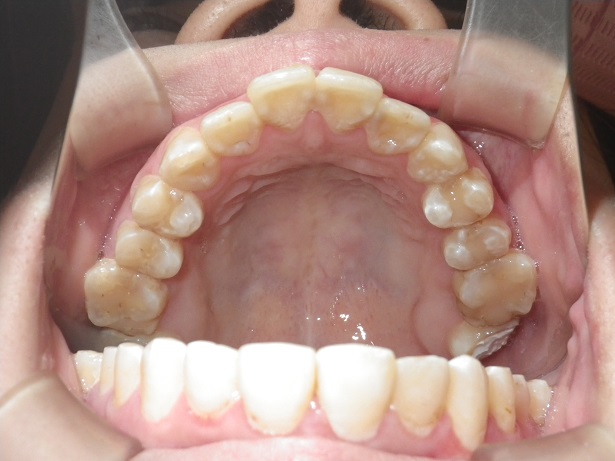

歯列矯正を開始するに当たり、歯科医院選びを間違うと以下の写真ようになる危険があります。

写真の症例ですが、小学3年から中学3年までやったそうです。(長いですね~)

痛くて途中で辞めたかったそうです。(無理やり拡大したからです)

高校受験があるので中断したそうです。(そこの先生はまだまだ続ける気だった、そうです。)

開始時期が早すぎます。小学6年で開始して2年で終了が通常のコースです。